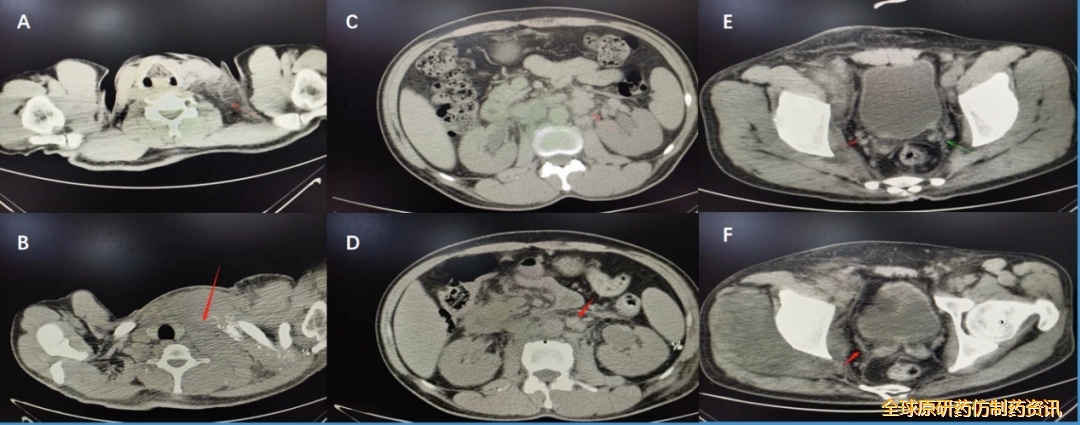

图3. 2023.03.29(A、B)、化疗4个周期(C、D、E、F)胸腹盆CT平扫检查结果